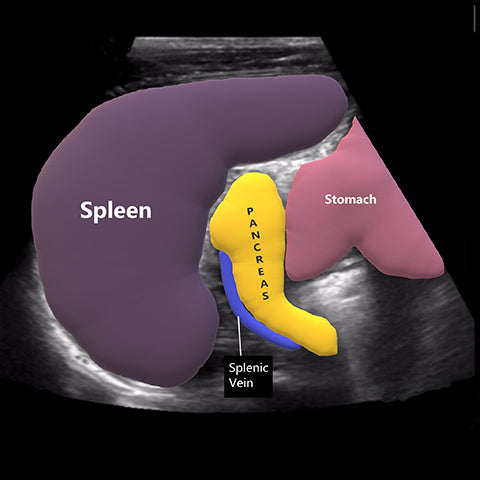

Organs with so many functions are not too big, and hidden deep in the abdomen of the human body, it is difficult to find problems when they occur.

Today we are thankful for clearly visualized pancreas .We can give you visual instruction.